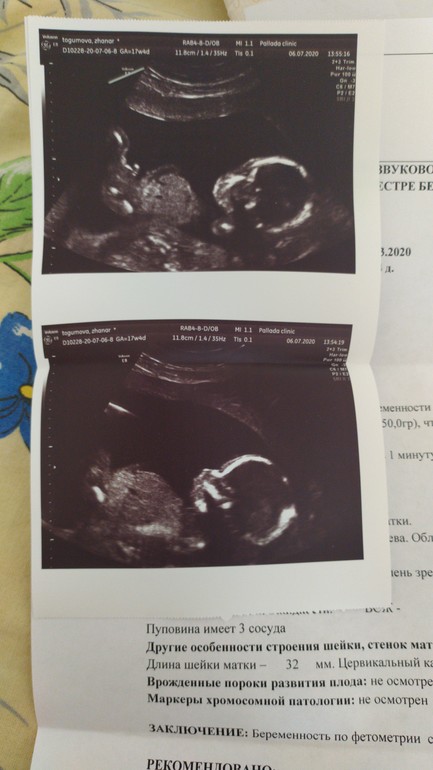

Определение пола в 15 недель 15 недель, у девочки отрос хвост :)